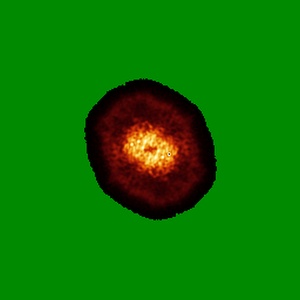

Structure of SARS-CoV-2 Orf3a in late endosome/lysosome-like environment, Saposin A nanodisc

Single-particle2.8 Å